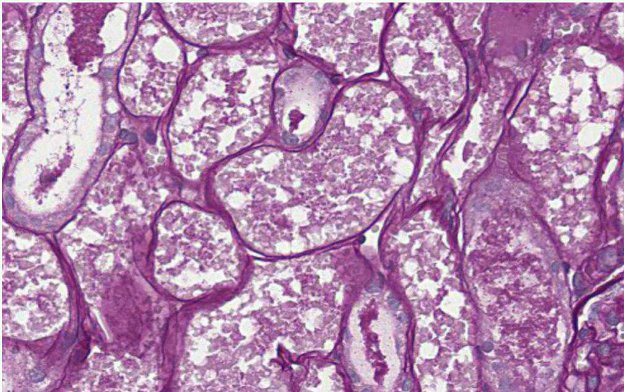

Le colorazioni istochimiche speciali e l’esame immunoistochimico sono delle tec- niche diagnostiche ancillari all’esame istopatologico, che possono essere richieste/suggeste per confermare la diagnosi o fornire informazioni aggiuntive rispetto a quanto osservabile con la sola valutazione istopatologica (con colorazione di routine Ematossilina ed Eosina).

Nella maggior parte dei casi si tratta di esami eseguibili sul campione più inviato in formalina e solo una piccola percentuale di colorazioni va eseguita su campione di tessuto non fissato in formalina e congelato. Anche se si differenziano significativamente per la metodologia, sempliciticamente siouldo aftermare che entrambé le tecniche hanno l’obiettivo di identificare/evidenziare strutture/componenti intra o extracellulari nellesezioni di tessuto.

Con tali metodiche, la sezione di tessuto viene sottoposta a reazioni chimiche attraverso le quali le strutture tissutali assumono colorazioni diverse a seconda di casa si vuole evidenziar.

Figura 1 - Colorazione istochimica PAS per evidenziare ife fungine (ben visibili in rosa intenso/fucsa), in un caso di aspergillo si nasale del cane.